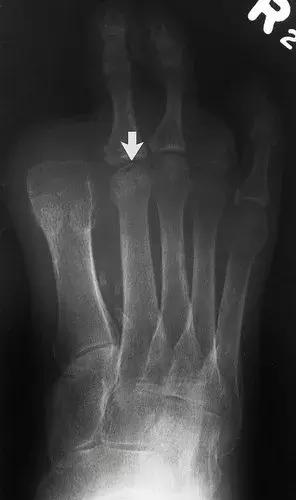

图16:60岁女性糖尿病人,胫骨关节的神经性骨关节病。侧位X线片显示胫骨远端和距骨(箭头)的再吸收和碎裂,明显的硬化,骨赘和骨膜炎(箭头)。